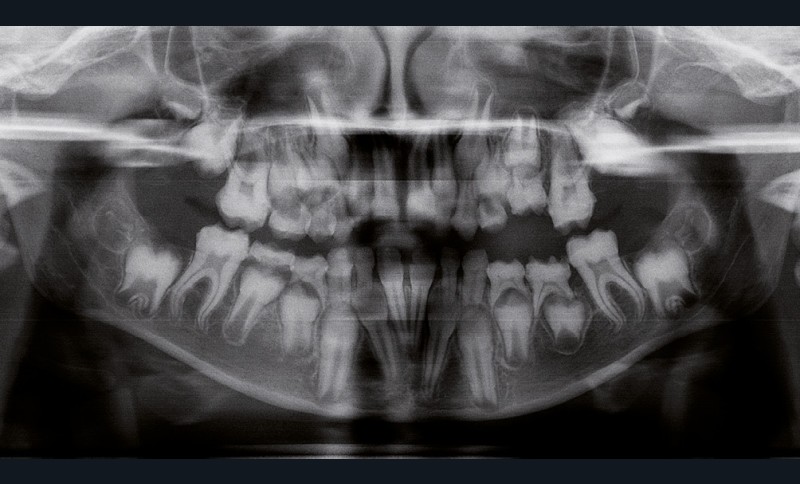

Il existe des anomalies dentaires (tabl. I) [1-12], mais aussi occlusales associées aux AI (fig. 1 et 2).

Selon de nombreuses études, l’anomalie occlusale la plus fréquemment retrouvée en association avec les AI est l’infraclusion antérieure, puisqu’elle est retrouvée chez 22 à 64 % des patients présentant cette affection, et encore plus chez les femmes [2,8,13-19]. Cette anomalie touche tous les types d’AI mais à des degrés très divers. Son incidence semble élevée dans les formes hypominéralisées, moindre dans les formes hypoplasiques et nettement moindre dans les formes hypomatures [8,17,18]. La sévérité de l’atteinte amélaire ne semble pas corrélée avec la présence ou l’intensité de cette malocclusion [17].

En 1982, Rowley et al. [18] ont montré que 44 % des patients atteints d’AI dans leur échantillon, présentaient un angle plan maxillaire (épine nasale antérieure – épine nasale postérieure) /plan mandibulaire (point gonion – point menton) supérieur à 34°, alors que la norme…